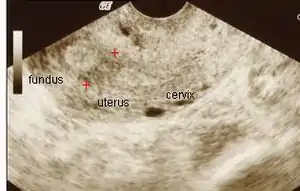

![]() Ультразвукові зміни при синдромі Ашермана (дослідження в сірій шкалі; червоними хрестиками означені спайки / злуки в матці) Ультразвукові зміни при синдромі Ашермана (дослідження в сірій шкалі; червоними хрестиками означені спайки / злуки в матці) | |